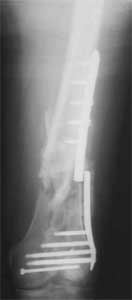

Attached are few examples from our Hospital:

A. Difficult reductions, even in retrograde nailing (my preference, easier control of "small" distal fragment) and it is much, much harder to do it anterograde (Alex, do you have one good case in your collection of anterograde nailing in very distal fractures - as you have suggested that I

should have done it in my previously posted case?

Malpositioning is much too common (recurvatum, varus - valgus).

B. Fixation loosening: distal cutting of the nail, non-unions do happen (cases attached).

Locking Plating has more distal screws than any nail, fixed angles and provides much better fixation, especially in osteoporotic bone.

A new toy is more interesting and fashionable. And anyway it is not panacea, i have already seen presentations with LISS failures like the attached one presented by D.Seligson. And people also demonstrated incisions say that the method is not so LESS invasive as it supposed to be.